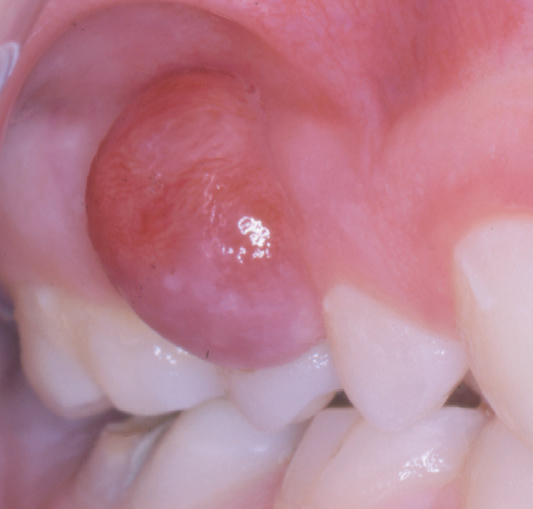

Kasus 1

En elleve år gammel pike var henvist fra kjeveortoped for fjerning av tumor mellom tennene 11 og 12. Det fremgikk av anamnesen at pasienten hadde hatt tannreguleringsapparatur i to år og at hun hadde dårlig munnhygiene. Det var fjernet en lesjon i samme region hos tannlege seks måneder tidligere, et residiv ble fjernet tre måneder senere hos lege ved en kirurgisk poliklinikk. Nå var det et nytt residiv. Det var mobilitet av tennene 11 og 12 og en rød-brun lesjon (figur 1a, b), som strakte seg fra marginalkanten til 5 mm fra apex på 11 og 12 (figur 1c). Lesjonen ble skrapt nøye ut, og det ble suturert en pakning over det blottlagte benet. Diagnosen PKCG ble bekreftet histologisk.

Figur 1. Kasus 1. PKCG mellom tann 11 og 12 (a, b) med tap av marginalt ben (c) hos en elleve år gammel pike.